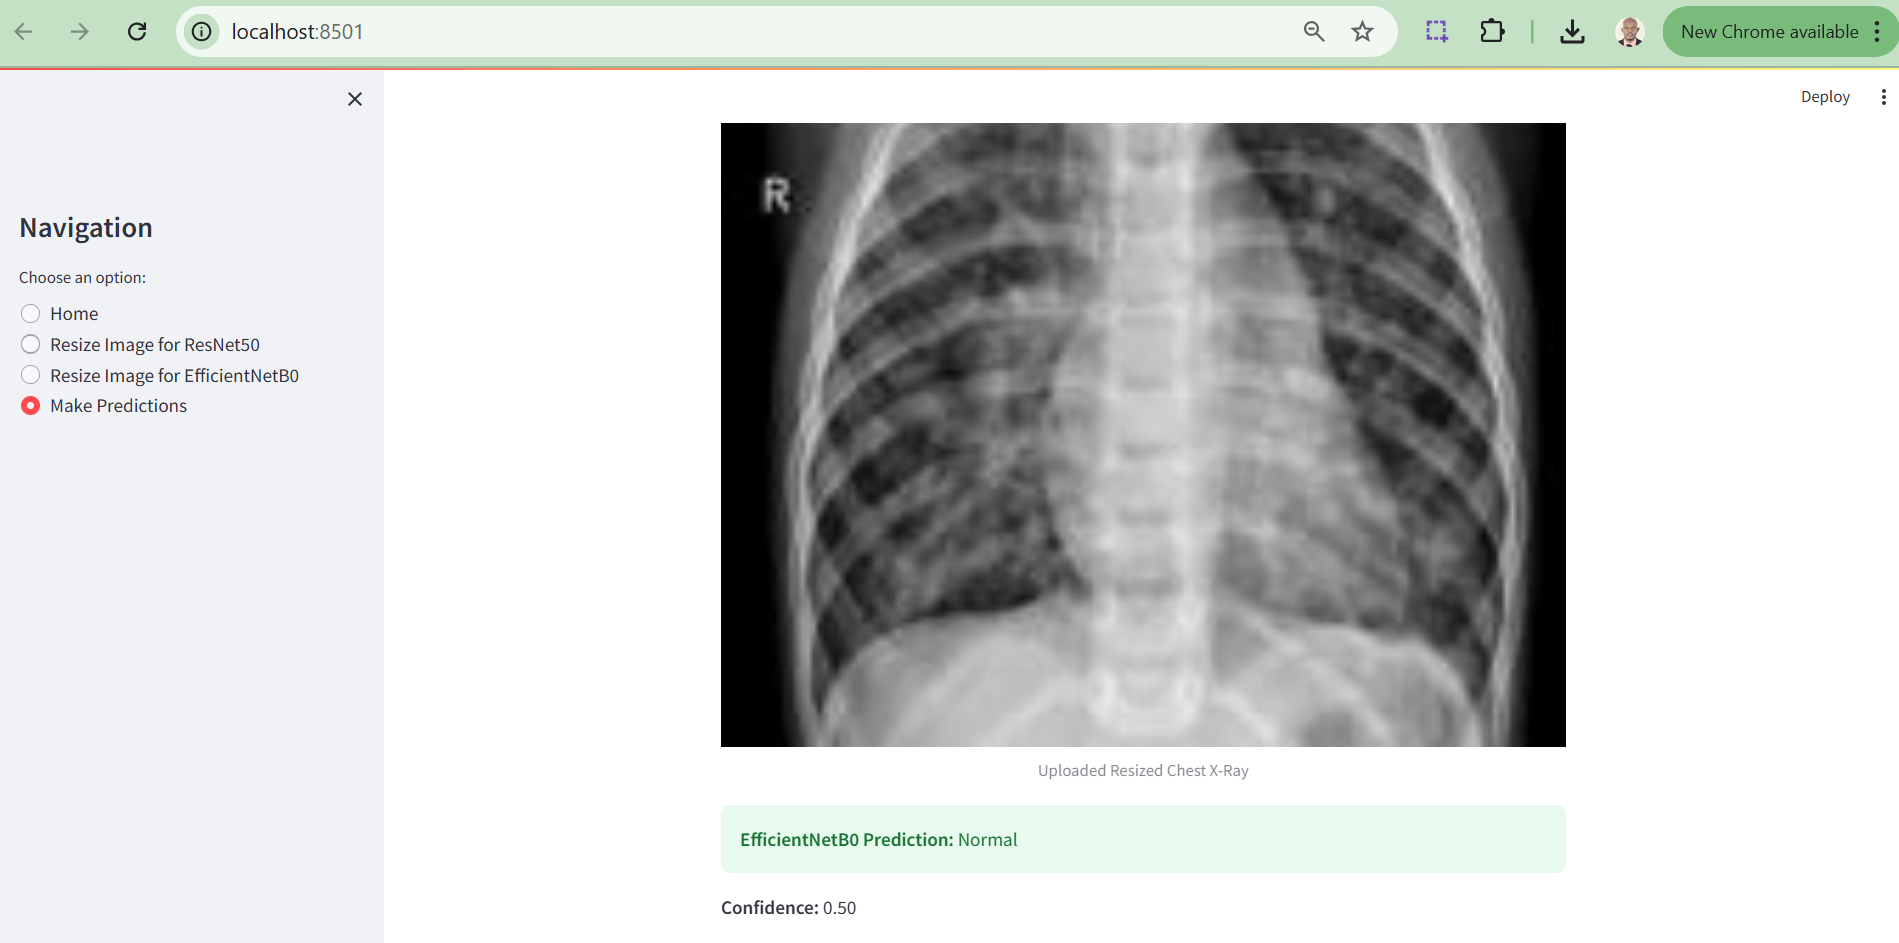

As part of this research, a web-based tool was developed to enable clinicians and researchers to easily utilize the trained deep learning models, ResNet50 and EfficientNetB0, for pneumonia detection. This application bridges the gap between advanced computational techniques and clinical usability by providing an interactive and user-friendly interface.

The tool allows users to:

i. Resize Chest X-Ray Images: Resize images to the required dimensions for each model (ResNet50: 224x224 pixels, EfficientNetB0: 150x150 pixels) using the "Resize Image" options in the sidebar.

ii. Upload and Analyze X-Ray Images: After resizing, users can upload the processed image and receive diagnostic predictions with associated confidence scores.

iii. Visualize Results: Users can compare the predictions of both models side-by-side, enabling insights into their performance and clinical applicability.

Below are screenshots of the tool interface:

Figure 9. Prediction Output Section

The results of this study reveal the strengths and limitations of leveraging deep learning models, EfficientNetB0 and ResNet50, for pneumonia detection. EfficientNetB0 demonstrated consistent performance when tested with properly resized images, highlighting its robust design for transfer learning and medical imaging tasks. However, its reliance on exact input dimensions underscores a limitation for real-world applications, where data may not always conform to predefined standards. ResNet50, on the other hand, showcased potential but suffered from implementation errors during prediction, a hiccup reflective of the constraints of research timelines rather than its architectural capability.

On a lighter note, the deployment of these models into a Streamlit web application offers a glimpse into the practical utility of AI in medical diagnostics. Though not without its quirks, one model excelling while the other remains uncooperative - it adds a humanising layer to this research. After all, even AI models can have bad days! Future iterations will refine these limitations, paving the way for a seamless integration of AI into clinical workflows.

Further notable limitation of this research’s web implementation is that the EfficientNetB0 model successfully generates prediction results only when users upload pre-optimized X-ray images, whereas the ResNet50 model currently fails to produce predictions due to an unresolved error. While significant efforts were made to address this issue, time constraints prevented its resolution within the scope of this research. This limitation will be prioritized and rectified in subsequent phases of the study to ensure a fully functional diagnostic tool.